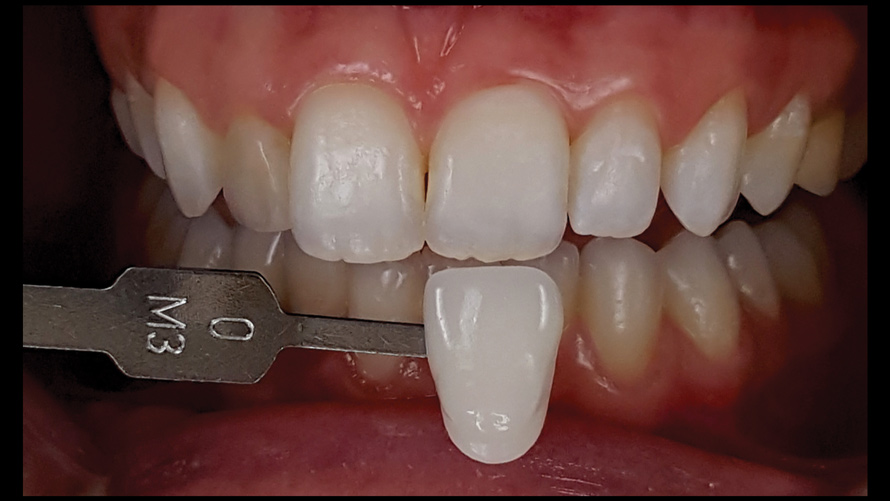

Shade Selection and Laboratory Communication

The most utilized intraoral photographs in the field of dentistry are perhaps those that capture shade information (Figure 18 and Figure 19). The analysis of color (ie, value, chroma, hue) in dentistry is a critical step in the fabrication of esthetic indirect restorations, such as all-ceramic crowns and porcelain laminate veneers. The ability to properly communicate this information with the dental laboratory is essential to ensure an appropriate shade match, a reduction in chairtime and overhead, and most importantly, a satisfactory patient experience and treatment outcome. In recent years, the use of polarized light photography as an aid in the shade selection process has become extremely popular. For some EALS devices, special polarizing filters have been specifically designed to fit over the light-emitting portion of the device (Figure 20 and Figure 21). The images produced using polarized light photography demonstrate an elimination or reduction in the specular reflection of hard and soft tissue, resulting in a matte-finish appearance of the dentition and gingiva. These types of photographs aid the ceramist in identifying areas of opacity and translucency, crack lines, hypo- or hypercalcification, and other internal features of the dentition that may not be readily visible without such a filter (Figure 22).

(18. and 19.) Tooth shade analysis of value, chroma, and hue taken with a smartphone and an EALS device.

Figure 18

Figure 19